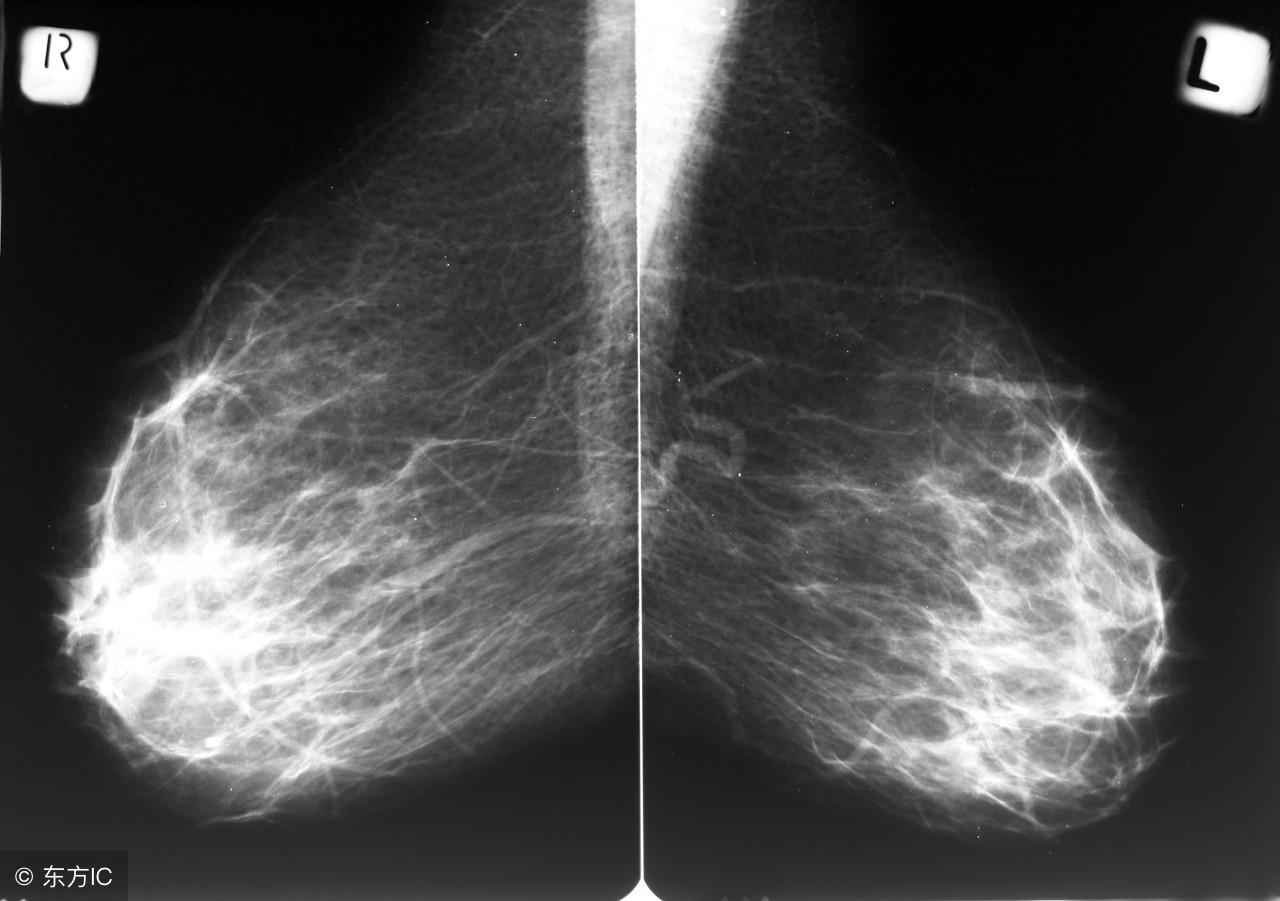

很多女性去医院检查,做彩超或是钼靶检查,最后结论里面都有“BI-RADS分级-3级”之类的表述,很多女性不知道是什么意思,有的甚至非常担心,下面我们就来看看BI-RADS分级是什么意思: